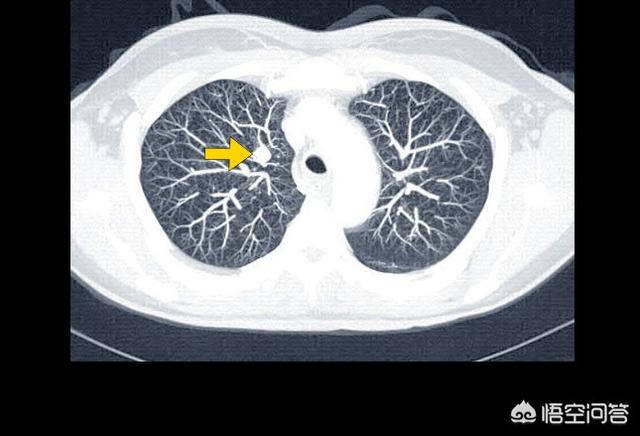

Ce patient n'avait que 39 ans, souffrait d'oppression thoracique et d'essoufflement, et on lui a diagnostiqué un adénocarcinome du côté droit du poumon, avec un épanchement pleural important et une perte de fonction de l'ensemble du poumon droit. Une affection aussi grave est plus fréquente chez les personnes âgées et, si elle n'est pas traitée, une insuffisance respiratoire se produira rapidement. Heureusement, elle est sensible à la thérapie ciblée et vit avec la tumeur depuis plus de trois ans maintenant, avec un épanchement pleural sous contrôle.